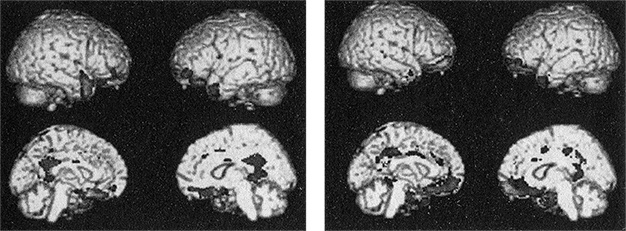

Я схватил стул и чуть отодвинул Прашантха от компьютера. У психопатов оказалась пониженная плотность серого вещества в глазнично-лобной коре, миндалевидном теле, гиппокампе, островке, височном полюсе и передней и задней поясной коре. Вся паралимбическая система была аномальна. Я даже не представлял себе такого эффектного результата. Он меня сразил.

Это был один из тех редких моментов в жизни ученого, когда полностью подтверждается гипотеза – гипотеза, которую мы со всей моей лабораторией оттачивали и совершенствовали годами. Я велел Эльзе запомнить этот день на всю жизнь. У психопатов действительно оказался аномальный мозг; мы получили надежное доказательство.

Рис. 8. Результаты первого анализа данных структурной МРТ по осужденным психопатам, собранные с помощью мобильного томографа. Затененные области – это те участки мозга, которые атрофированы у взрослых психопатов-преступников мужского пола. Они соответствуют большей части паралимбической системы (см. при-меч. 3)

Я распечатал копии карт и побежал вниз, чтобы показать их своему коллеге Винсу Калхуну. Он задал несколько общих вопросов, дважды проверил мои выводы и потом попросил копию скрипта, который написал Прашантх для параллельной обработки данных. Его тоже впечатлила и находчивость Прашантха, и наши результаты.

Я в том же месяце представил данные о плотности мозга психопатов на заседании исследовательской сети при Фонде Макартуров. Профессора права и судьи долго смотрели на изображение, обдумывая, какие все это может иметь следствия. Я напомнил, что мы установили корреляцию, но не причинно-следственную связь.

– Если вашу руку повесить на перевязи на груди и обездвижить, у вас со временем атрофируется бицепс. Если потом вы придете к врачу, он, скорее всего, спросит, всегда ли у вас была атрофированная рука, или это произошло из-за того, что вы ею не пользовались. Врач не может определить разницу, просто осмотрев руку. Мозг тоже в своем роде мышца. Плотность серого вещества иногда меняется со временем. Значит, только по этим данным нельзя сказать, атрофирован ли мозг психопата с рождения, или он атрофировался со временем под влиянием жизненного опыта. Иными словами, если не пользоваться какими-то частями мозга, они в конце концов могут уменьшиться, перестать работать и даже погибнуть.

Наши результаты снова не показали причинно-следственной связи; то есть мы не могли сказать, что психопатическое поведение – это прямое следствие атрофии мозга. Но я уже планировал следующий анализ, который, может быть, ответил бы на этот вопрос.